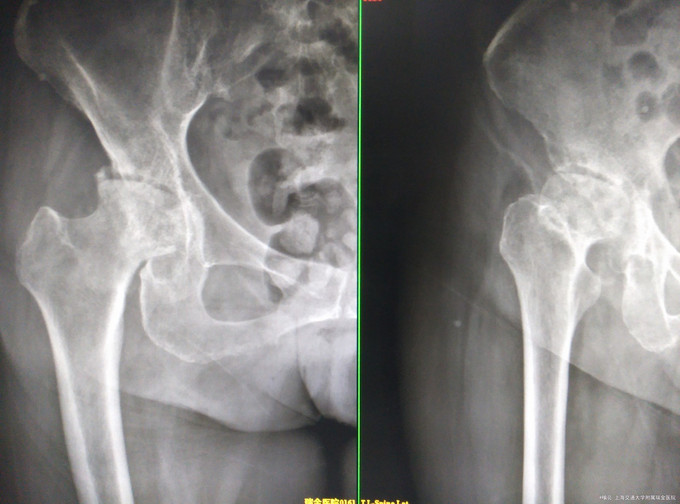

右侧腹股沟区疼痛2年。 右侧腹股沟区疼痛2年。疼痛与活动相关,起病初休息后或服用止痛药物后疼痛可获得缓解。近期疼痛逐渐加重,白天活动后疼痛至夜间亦不能缓解。须长期靠止痛药物维持日常生活。患者自发病以来,神清,精神可,胃纳可,睡眠欠佳,二便无殊,体重无明显改变

神清,精神可,双下肢无明显肿胀,右侧髋关节局部轻压痛(+),叩痛(±),活动受限,4字征(+),轴向叩痛(—) 。 辅查: 右侧髋关节髋臼发育不良,髋关节退行性病变

DDH继发髋关节退变 右侧THA